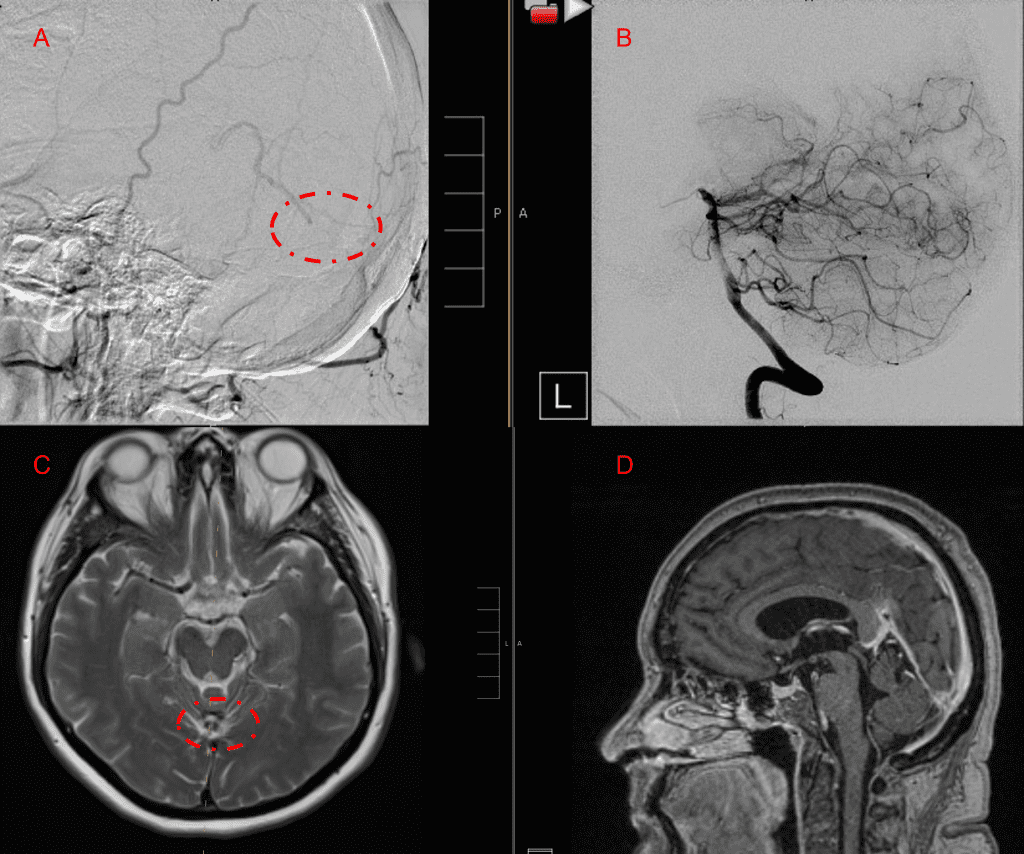

Embolization was successful at immediately reducing the pressure into the Aneurysmal Varix with greater than 90% reduction in A-V shunts. After an intensive period of critical care monitoring and care for her initial brain hemorrhage, she made a near complete recovery with mild intermittent left sided paresthesias and generalized deconditioning. After receiving inpatient and outpatient Acute Rehabilitation, Physical, and Occupational therapy, she completely recovered all of her Activities of Daily Living (ADLs) at 3 months and achieved an modified Rankin Scale (mRS) of 0. On follow-up angiography, small residual low flow A-V shunts were identified and targeted for Gamma Knife Radiosurgery (Figure 5 and 6).

Figure 6. MRI and Catheter Angiograms precisely localize the residual A-V shunts vessels to perform Gamma-Knife Radiosurgery to deliver therapeutic doses to the targets.